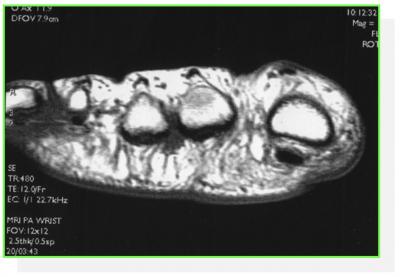

On peut avoir recours aux scanners, échographies et IRM pour confirmer les lésions des articulations, des tendons, des plaques plantaires

IRM : Bursite , rupture de la plaque plantaire